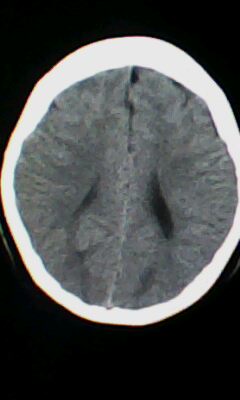

标题: CT25338:女 14岁 3岁时检查为脑积水 现在发育滞后 偶有尿失 [打印本页]

标题: CT25338:女 14岁 3岁时检查为脑积水 现在发育滞后 偶有尿失

颅脑ct轴位平扫颅内未见明确异常。

脑皮质增厚,发育异常!

左侧灰质异位

左侧颞枕叶区密度异常?